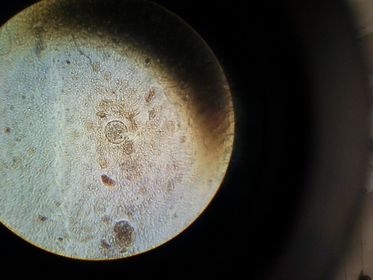

1.- Naegleria fowleri

1.- naegleria